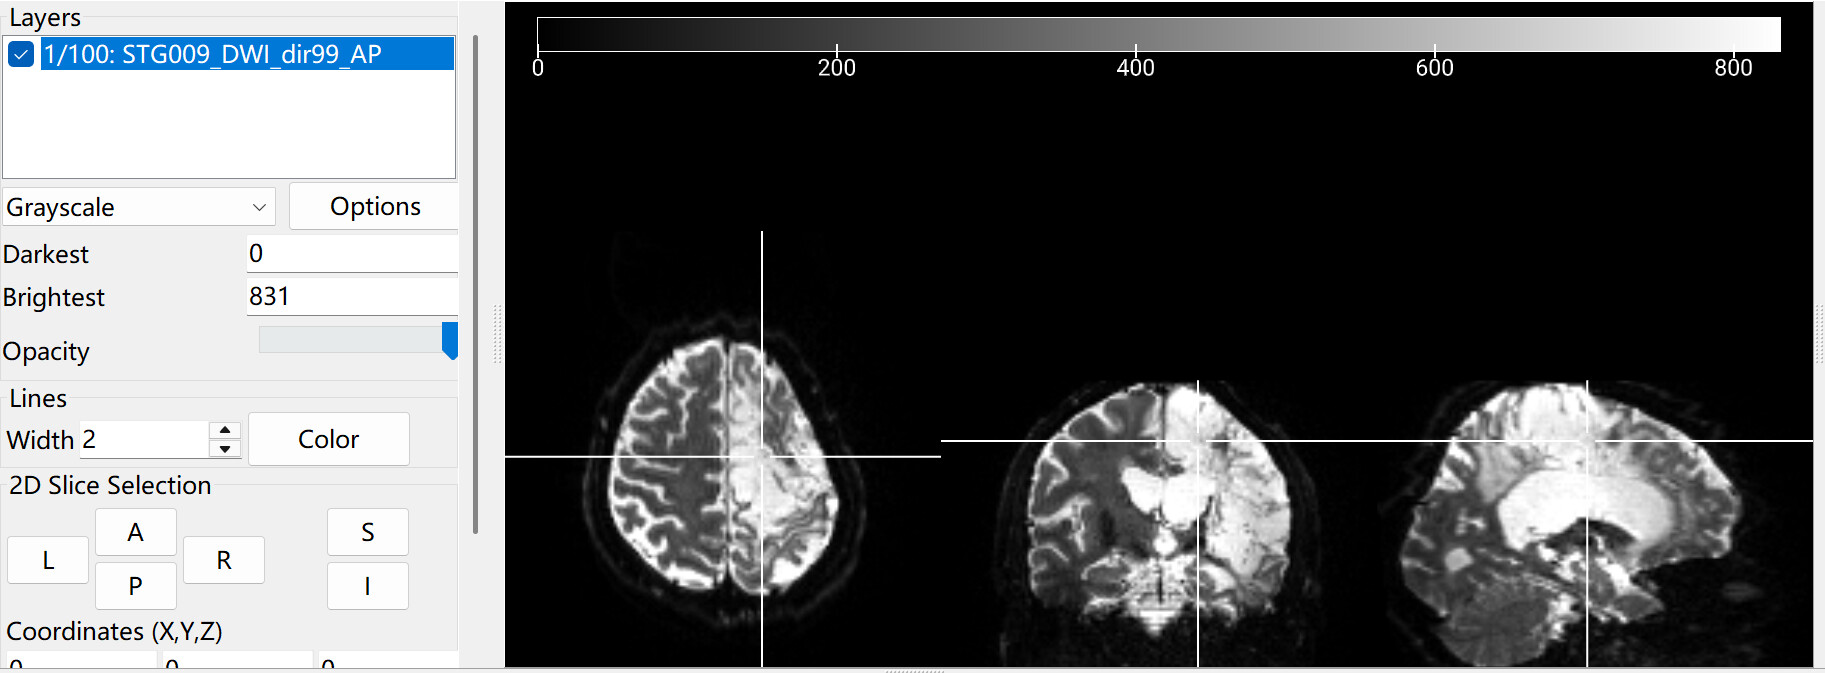

The following is the raw diffusion data of example 1. These data come from stroke patient, so his brain exhibit this characteristic. In this situation, will the above situation always occur when handling hcp_diffusion? If it’s possible to avoid data loss, I’d still like to try my best to preserve the data.